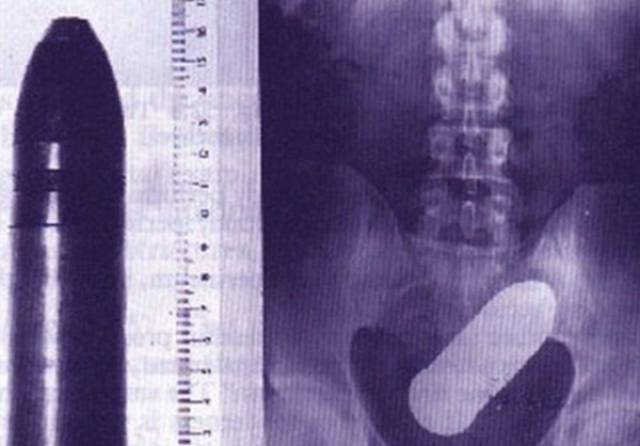

An artillery shell in someone’s rectum.